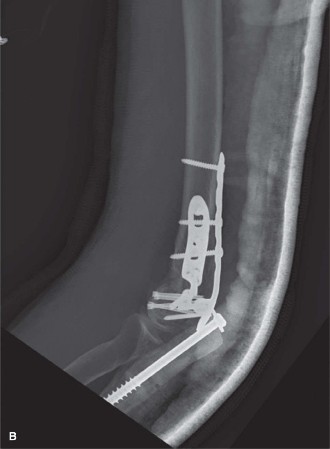

- Orthogonal (90/90) Plating:

- A plate is applied to the medial aspect of the medial column, extending proximally along the supracondylar ridge.

- A second plate is applied to the posterior aspect of the lateral column, extending proximally along the lateral supracondylar ridge.

- Screws from the lateral plate are directed medially into the medial column, and vice versa. This creates a strong construct resisting varus/valgus and shear forces.

- Caption: Orthogonal (90/90) plating construct. Note the plate on the medial epicondyle and the plate on the posterolateral column, with screws crossing into the opposing column.